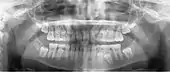

Галерея

Минимально смещенный перелом правой нижней челюсти. Стрелка отмечает перелом, корневой канал на центральном резце, зубы слева от перелома не соприкасаются